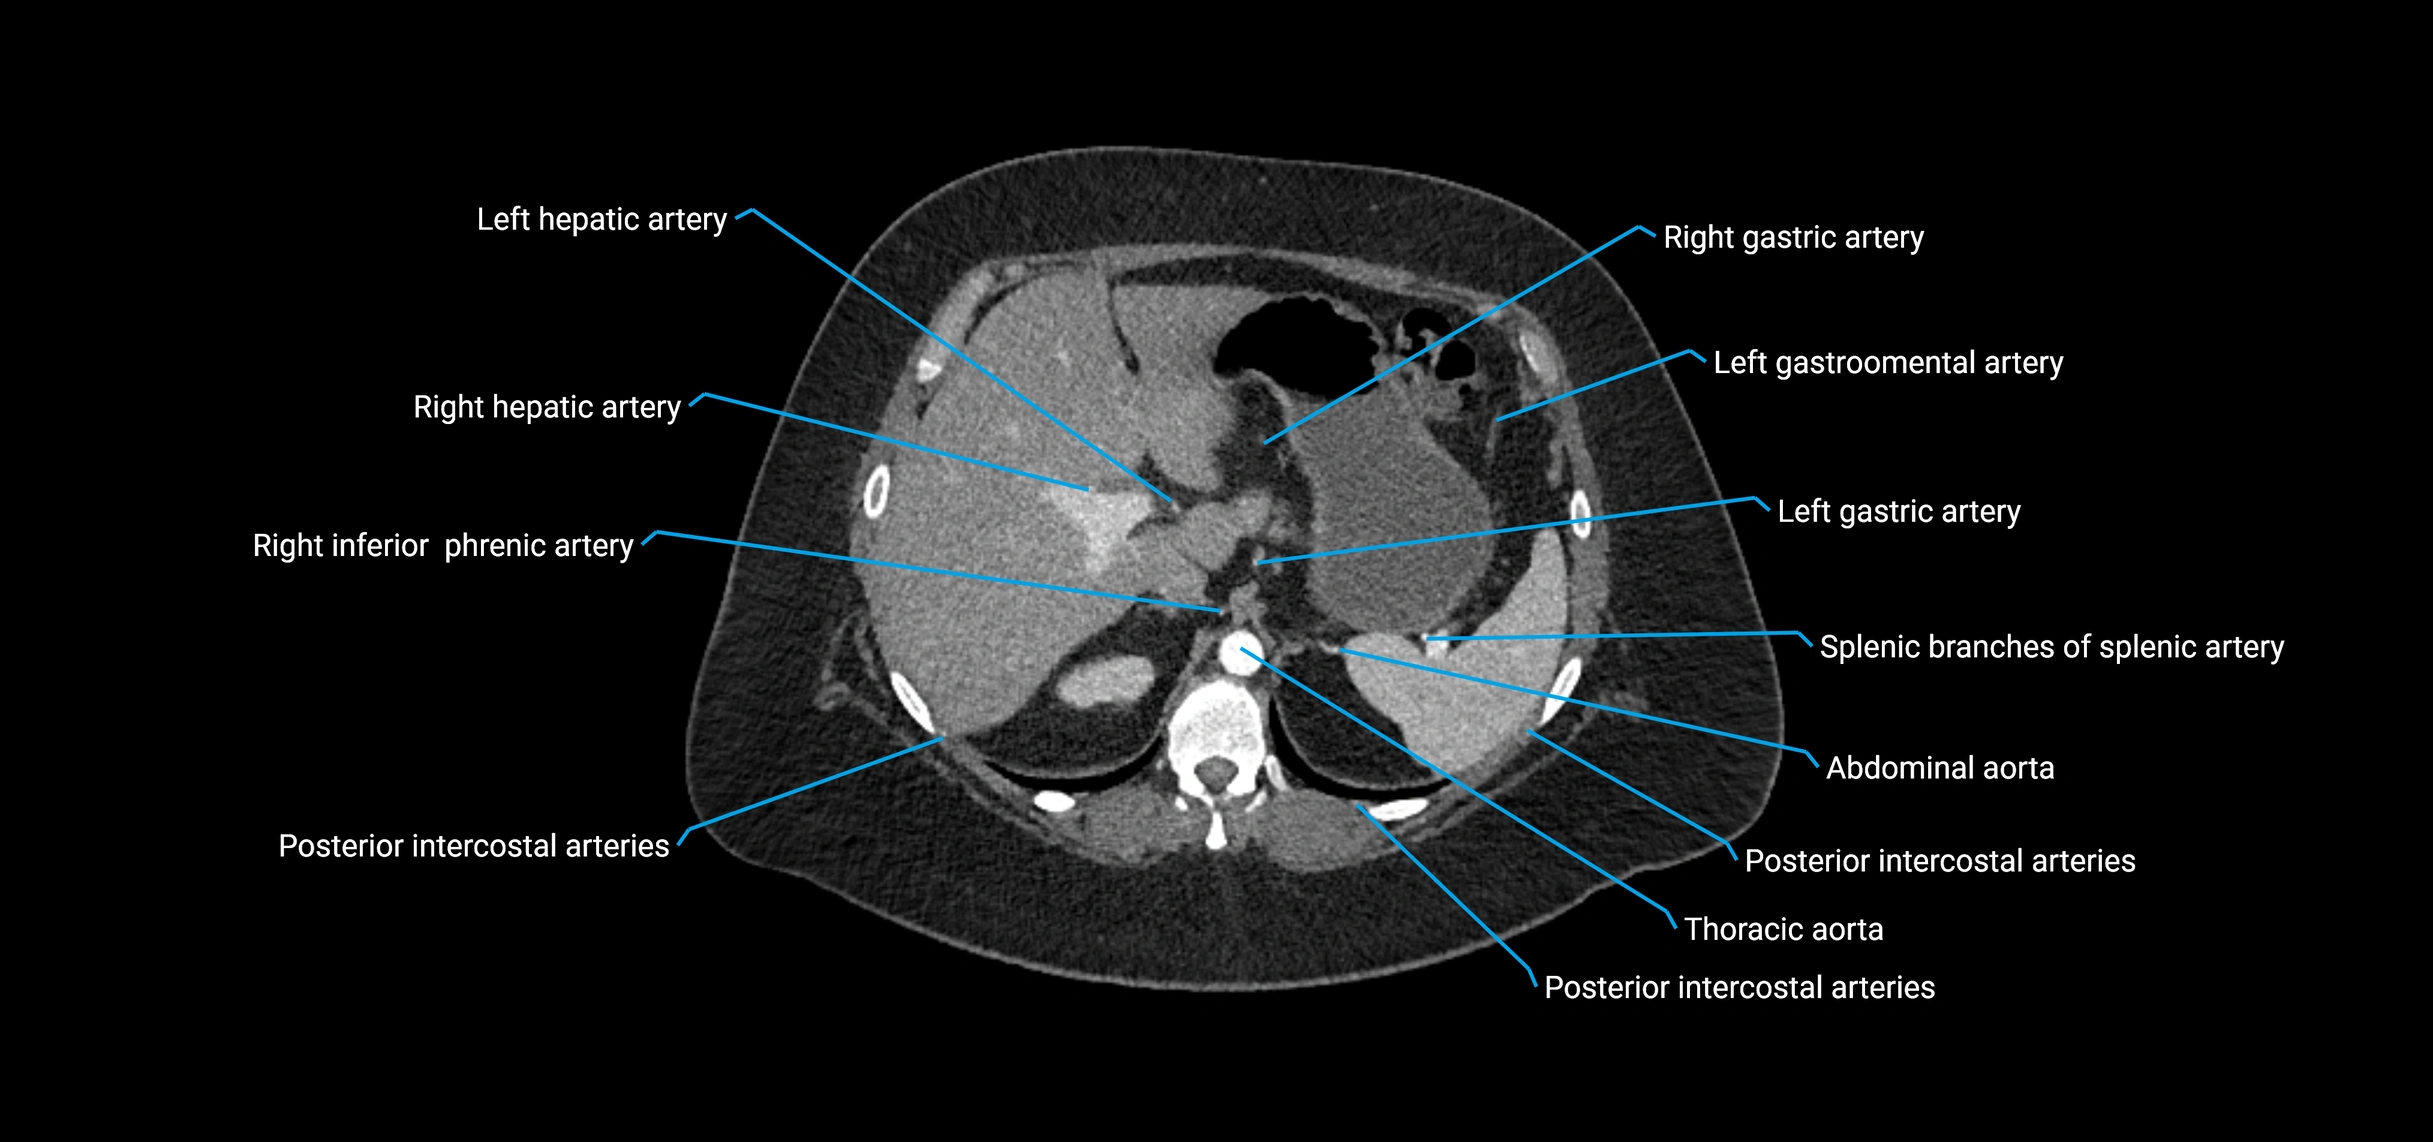

Contrast-enhanced CT (CTA):

• Gold standard for abdominal aortic imaging

• Provides excellent detail of lumen, wall, aneurysm, thrombus, and branch vessels

• Multiplanar and 3D reconstructions help in aneurysm measurement, stent graft planning, and dissection evaluation

• Detects acute rupture, traumatic injury, or occlusion with high sensitivity